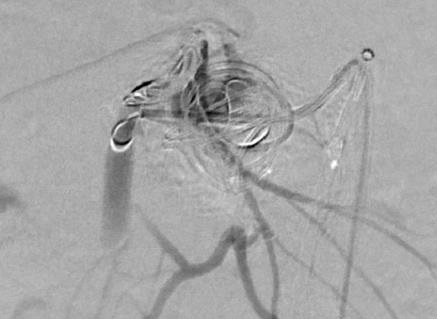

栓塞后弹簧栓子逸出至右肺静脉 |

栓塞后弹簧栓子逸出至右肺静脉 |

|

弹簧栓子在左心房“狂”跳 |

没啦? |

去哪儿啦? |

在这儿! |

嵌在股深浅动脉分叉处 |

弹簧栓子被移除 |